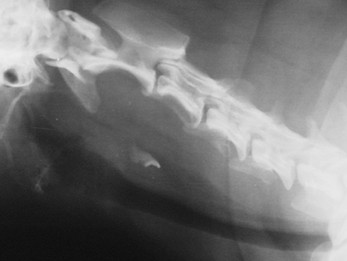

כלב עם חתיכת עצם תקועה בושט

כלב שהגיע עקב חוסר אכילה של מספר ימים וכאב בזמן נסיונות אכילה ובליעה. בבדיקה נמצא כי לכלב כאב הצואר. בצילום רנטגן ניתן לראות שבב עצם תקוע...